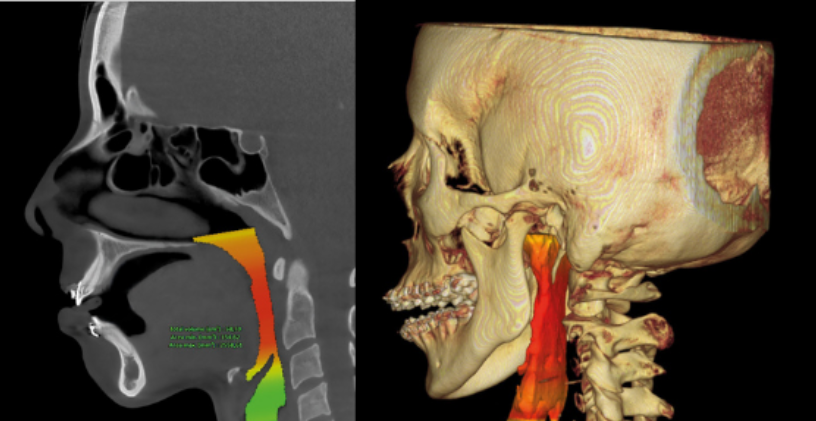

Evaluación de la articulación y la mordida

Evaluar la articulación temporomandibular es esencial para garantizar la funcionalidad adecuada y evitar problemas.

Diagnóstico Vía aérea y otras patologías

El diagnóstico de la vía aérea y estructuras relacionadas es crucial para mejorar la calidad de vida.